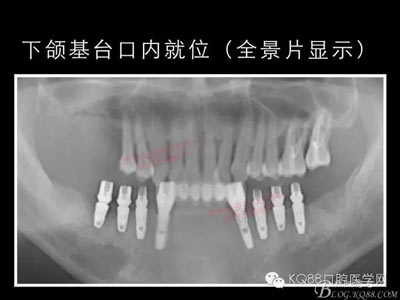

下面的種植病例是為患者提供全口牙齒治療修復完整過程的下頜部分,我們門診和患者共同配合下目前取得了較好的修復效果,即將開始的上頜牙齒治療修復過程仍然艱辛。